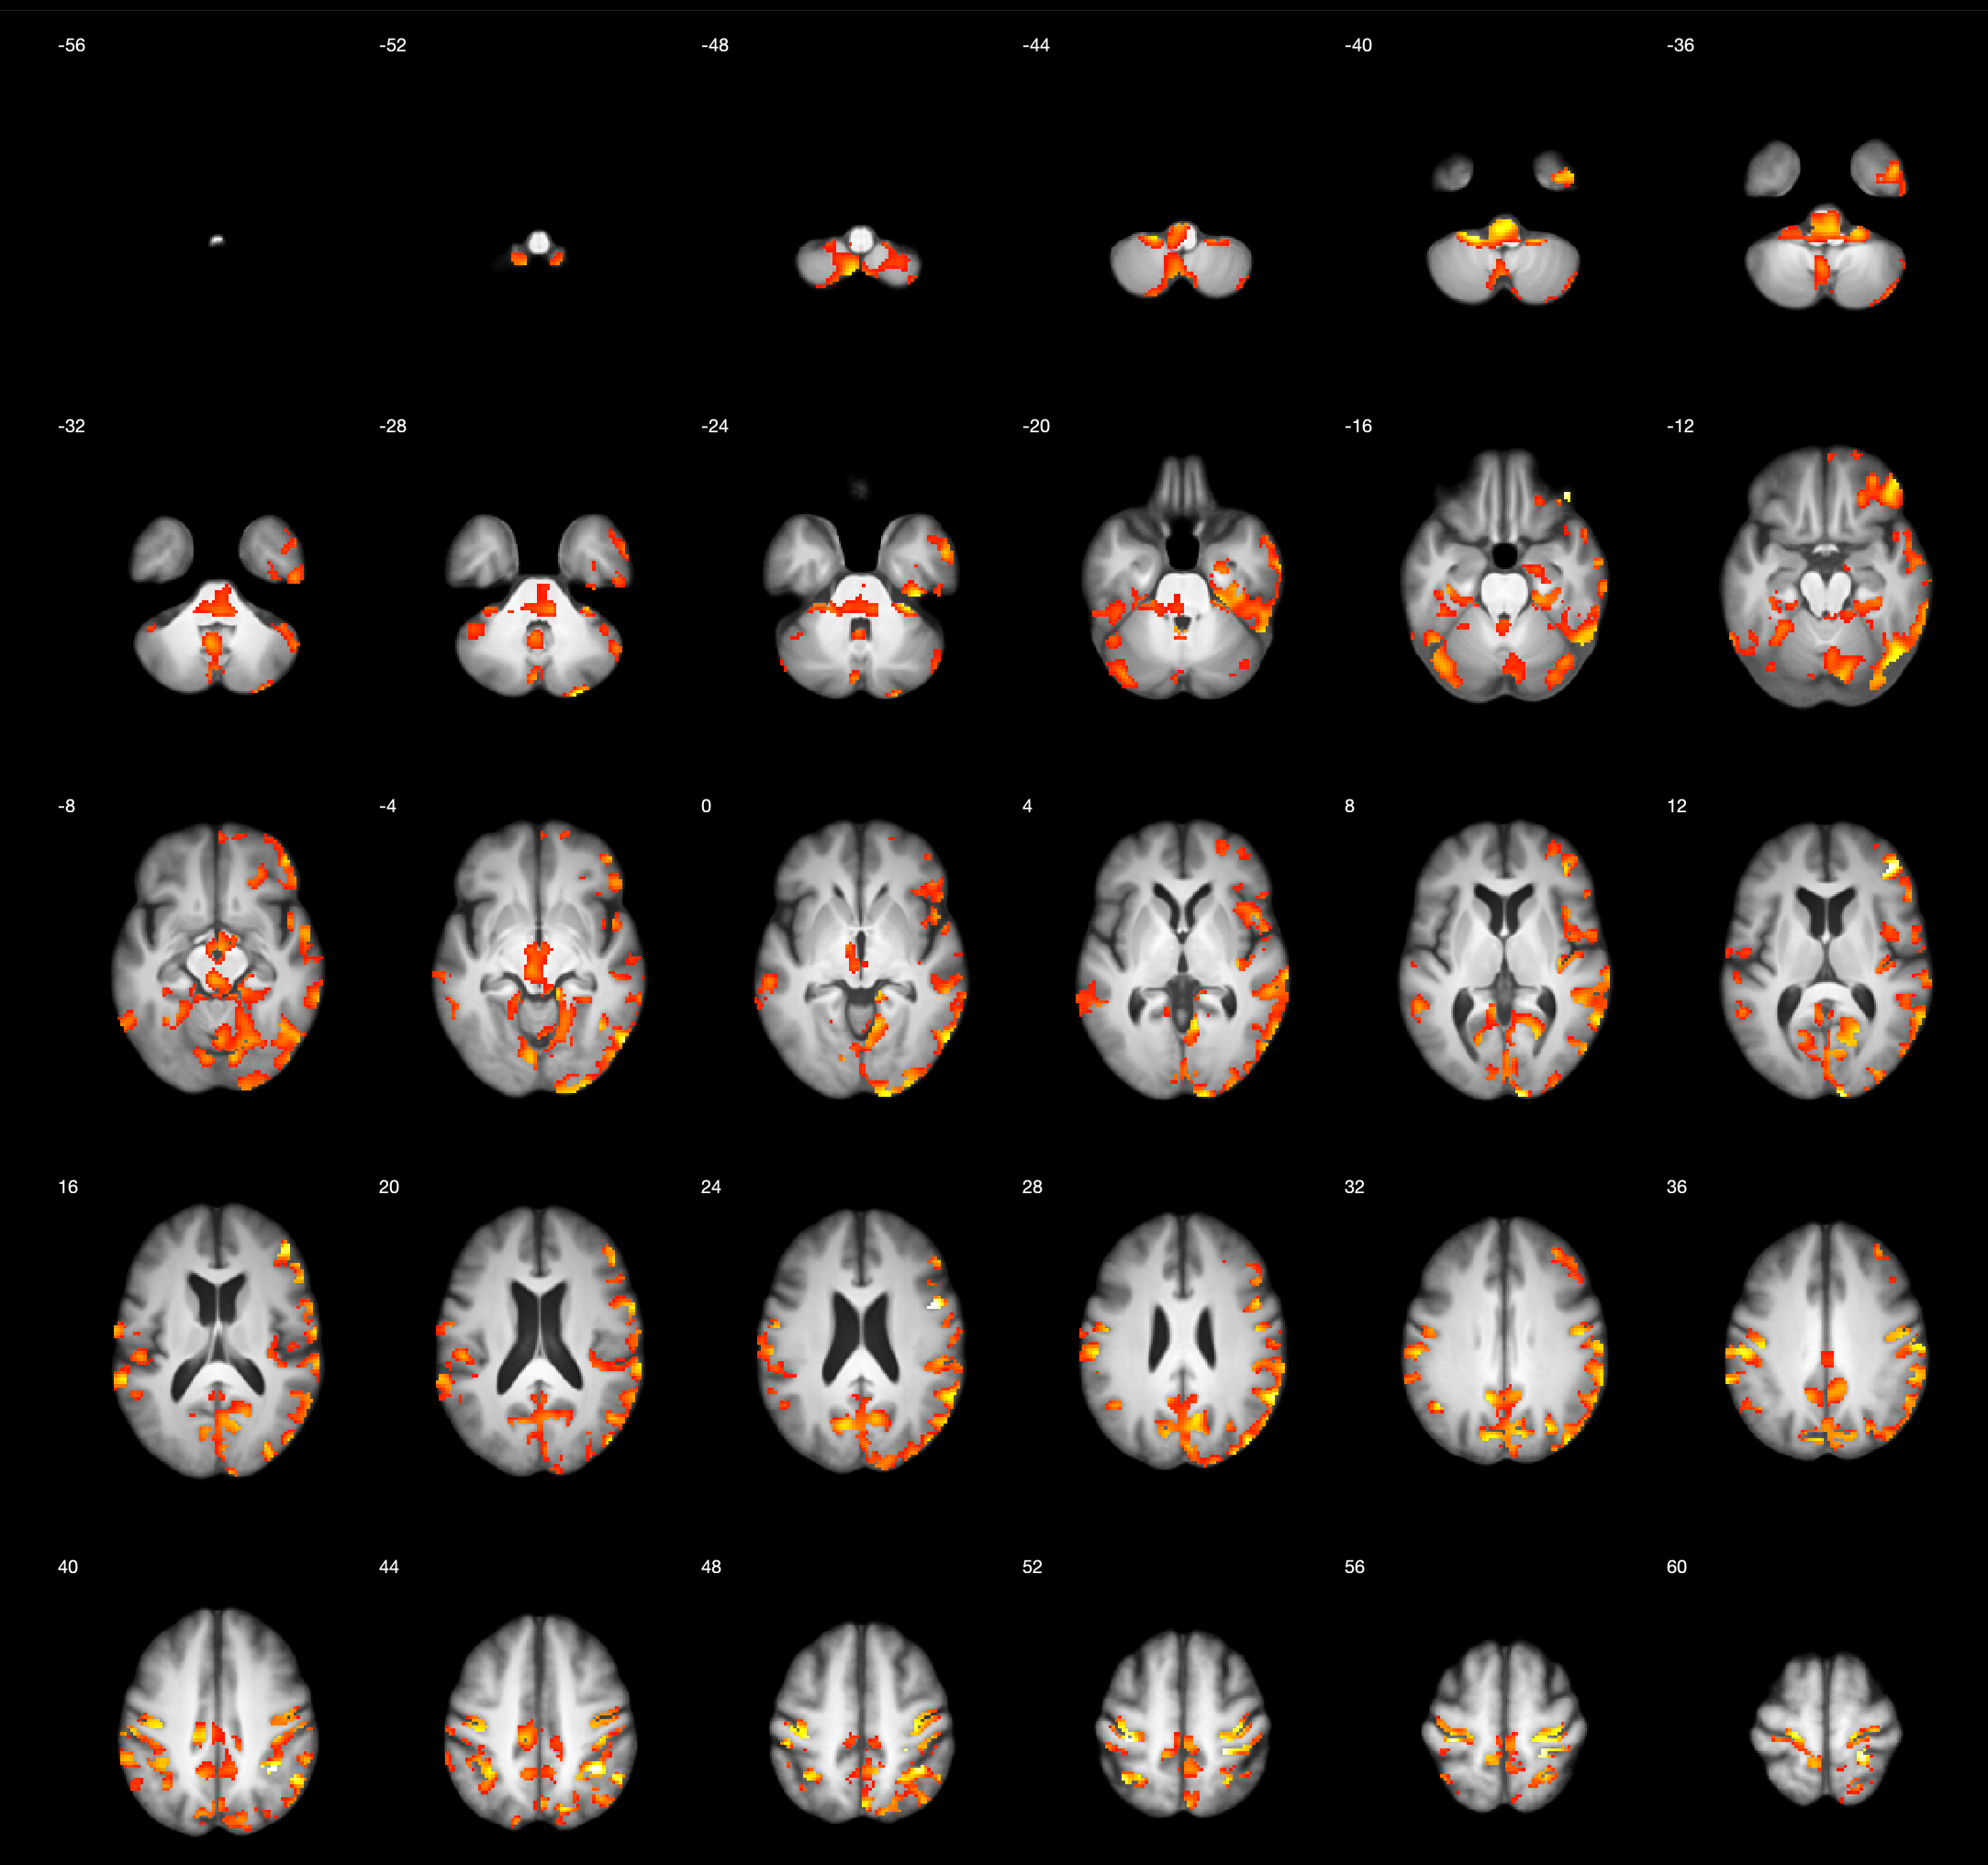

Results: Voxel-based analysis showed significant cholinergic vulnerability in right temporo-occipital junctions, right superior temporal and temporal operculum auditory cortices, right dorsolateral prefrontal cortex, right orbitofrontal, posterior & anterior cingulum, right superior parietal cortex, right inferior colliculus, right superior and posterior cerebellar hemisphere, superior vermis, retrosplenial cortex, right occipital cortex (cluster-level FWER corrected P<0.05, see figure 1). A mask of statistically significant voxels was used to extract the mean [18F]FEOBV uptake value for regression analyses. A post-hoc regression analysis showed that greater central cholinergic system integrity associated with better SPiN performance (see figure 2) independently of pure tone audiometry (β=-0.507, p=0.013), accounting for an additional 25.4% of the variance in SPiN.

Conclusion: Greater cholinergic system integrity, predominantly lateralized to the right hemispheric auditory, lateral frontal, and multisensory cortices associated with better performance on the speech-perception-in-noise task. Prior works show that the right hemisphere appears to predominantly contribute to speech perception in noisy as compared to quiet conditions 2–4.

Figure 1.